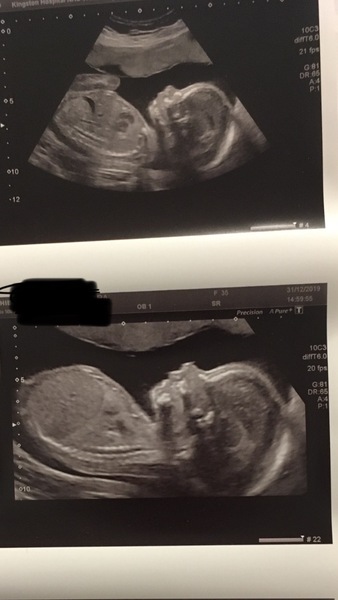

Sorry been quiet been really busy. Had gender scan today and got stitch thursday

My girlie. Also have an anterior high placenta but have felt her since 18wks if not a bit earlier and DH felt her Boxing Day.